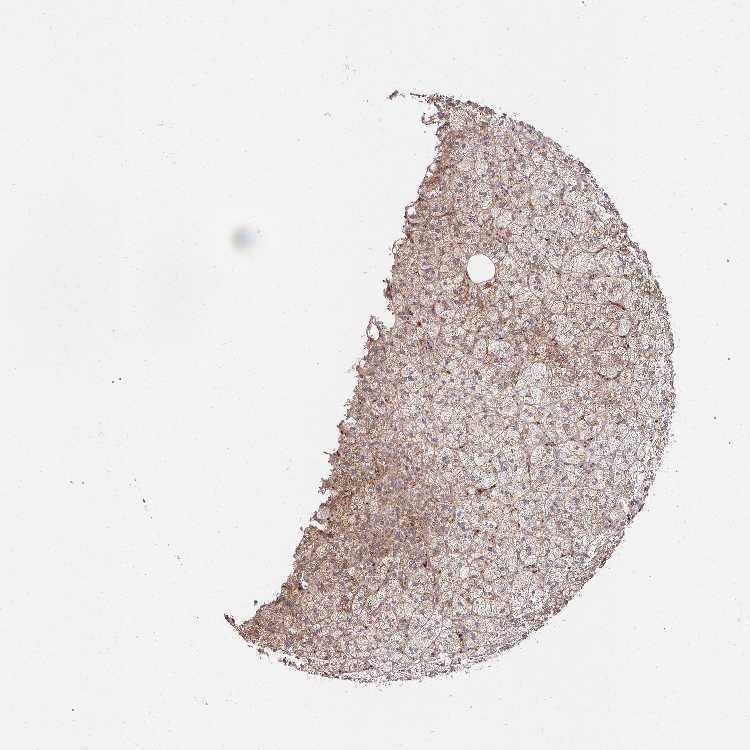

ADRENAL GLAND - Antibody stainingi

Antibody staining in the annotated cell types in the current human tissue is reported as not detected, low, medium, or high, based on conventional immunohistochemistry profiling in selected tissues. This score is based on the combination of the staining intensity and fraction of stained cells.

Each image is clickable and will lead to virtual microscopy that enables deeper exploration of all samples and also displays staining intensity scores, fraction scores and subcellular localization as well as patient and tissue information for each sample.

Antibody HPA046979Antibody HPA054254Antibody CAB025901

Glandular cells MediumMediumHigh